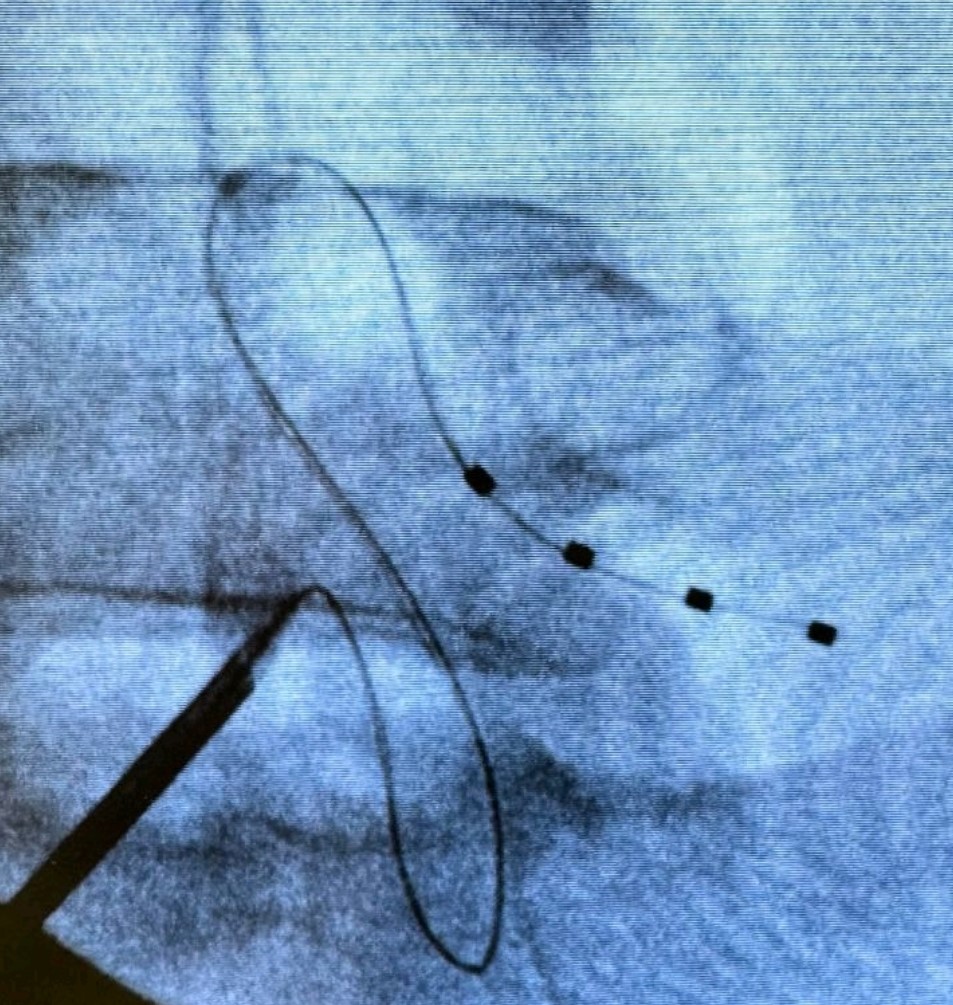

Ποια είναι η θεραπευτική διαδικασία

Η τεχνική της διέγερσης του DRG είναι σχεδόν πανομοιότυπη με τη τεχνική διέγερσης του νωτιαίου μυελού. Ωστόσο, στόχο της νευροδιέγερσης εδώ αποτελεί το συγκεκριμένο γάγγλιο και όχι ο νωτιαίος μυελός. Τα γάγγλια της ραχιαίας ρίζας βρίσκονται στα μεσοσπονδύλια τρήματα.

Η διέγερση του DRG αφορά στην εμφύτευση ηλεκτροδίου που στέλνει ηλεκτρικά ερεθίσματα στη συγκεκριμένη περιοχή. Οι ώσεις αυτές διακόπτουν τη μετάδοση των σημάτων πόνου από το περιφερικό προς το κεντρικό νευρικό νευρικό σύστημα. Με απλά λόγια, η διέγερση του γαγγλίου τροποποιεί την αντίληψη του πόνου. Πριν την τελική εμφύτευση του ή των ηλεκτροδίων και τη σύνδεση αυτών με τη γεννήτρια, προηγείται διάστημα δοκιμαστικής διέγερσης με φορητή, εξωτερική γεννήτρια.